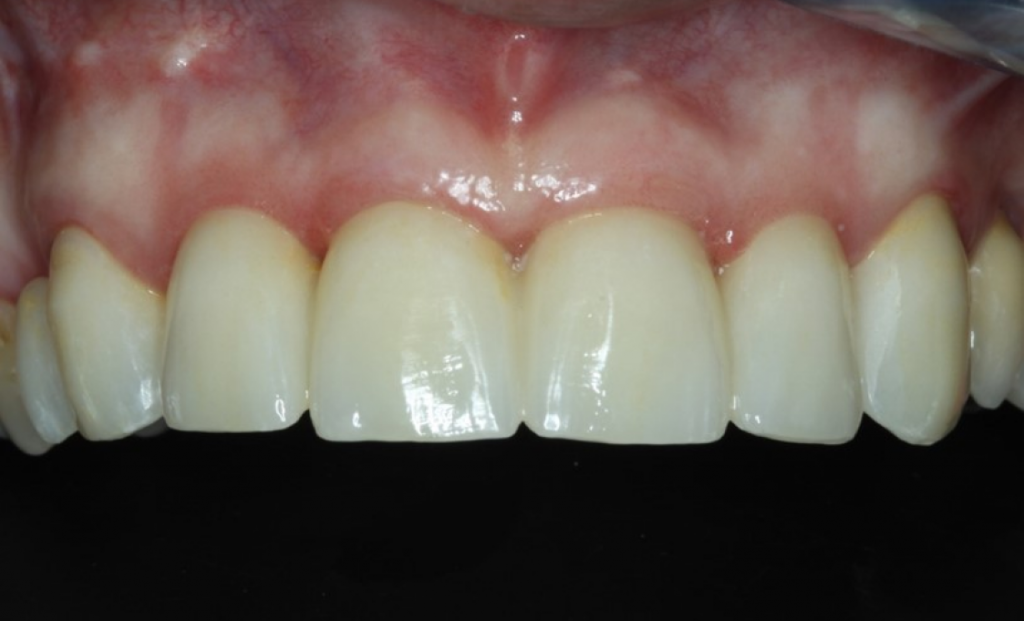

Рис. 23 Итоговый результат лечения с установленным мостовидным протезом 12-22 на имплантатах. Обратите внимание на естественный профиль ткани после извлечения 12, 11, 21 и 21